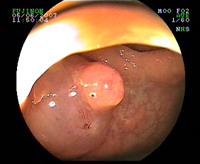

Gros polype pédiculé

Polype pédiculé